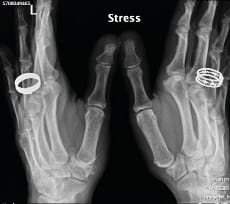

Eaton’s views are the same as Kapandji’s frontal view, except that in the Eaton series the images are comparative (Figure 4), which means that a stress view (Figure 5) is taken so that the joint space can be assessed for any collapse when put under stress.

The value of dynamic views is illustrated very clearly in Fig. 12, showing a Dell stage II, Eaton stage 3, TMA 1, TMI 1, STT 0 joint, which, when seen under stress, suddenly becomes Dell stage II (unchanged) Eaton stage 3 and TMA 3, TMI 1, STT 0 (Figure 13). This demonstrates that Allieu’s classification has greater precision for the TMA [8] Vigouroux F, Rabarin F, Jeudy J, Bigorre N, Saint Cast Y, Pechmajou L, Raimbeau G. Peritrapezial osteoarthritis: Inter – and intraobserver reliability of the Allieu classification. Hand Surg Rehab 36 (2017) 363-367 .